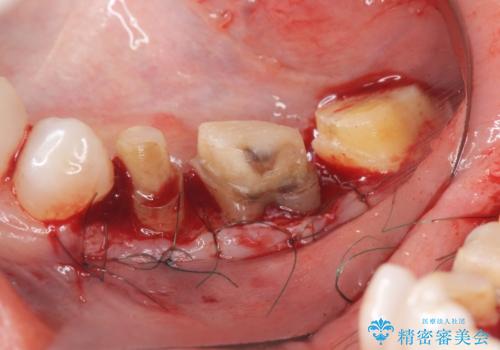

クラウンやレジン下に再発していた虫歯を丁寧に除去したのち、歯ぐきの腫れが改善が見られないため歯周外科を行い歯ぐきの状態を整えたのちにジルコニアクラウンを製作していきます。

クラウン治療を行う場合歯ぐきの腫れが、クラウン製作の精密さにおいて問題点となることがあります。

このような場合、歯周外科を行うことでクラウン周囲の歯茎の状態を整備し精度に優れる治療を行うことができます。